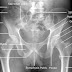

Proyeksi AP

Posisi Pasien : Pasien diposisikan supine

Posisi Objek : - kaki ekstensi

- atur pelvis pada posisi true AP (Pedis menghadap ke atas)

- atur pelvis pada pertengahan kaset

- kaki dibuka sekitar 20-24 cm, kemudian ujung jempol kaki disatukan

- pastikan nantinya tidak ada gambambaran yang terpotong

Central point (CP) : pertengahan antara SIAS dan simpisis pubis

Central Ray (CR) : vertikal tegak lurus kaset

FFD : 100 cm

Kaset : 35x35cm